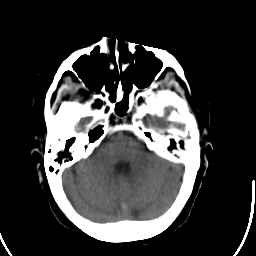

Stroke CT #1 -- Slice #6

[Home][Help][Clinical] Slice 6